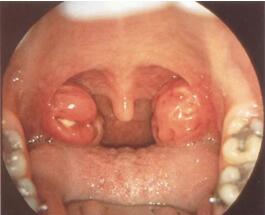

咽后脓肿为咽后隙的化脓性炎症,按发病机制可分为急性和慢性两种。

咽后隙位于椎前筋膜与颊咽筋膜之间,上起颅底,下至第1、2胸椎平面,两侧仅以薄层筋膜与咽旁间隙相隔。咽后隙在中线处被咽缝分为左右两侧,且不相通。每侧咽后间隙中含有咽扁桃体、咽鼓管扁桃体及鼻腔鼻窦等区域所属的淋巴结,3个月至3岁以前婴幼儿较多,儿童期逐渐萎缩,至成人只有极少淋巴结。咽后间隙是咽后脓肿的好发部位。

急性型起病较急,有畏寒、高热、咳嗽、吞咽困难等症状,小儿拒食,吸奶时吐奶或奶汁返流入鼻腔或呛咳不止,说话及哭声含糊不清,如口内含物状,常有呼吸困难,其程度视脓肿大小而定,入睡时有鼾声与喘鸣声。患者头常有偏向病侧以减少患侧咽壁张力,缓解疼痛,并扩大气道腔隙。如脓肿增大,压迫喉入口,或炎症累及喉部,则呼吸困难加重。严重病例可出现脱水,衰竭等现象。